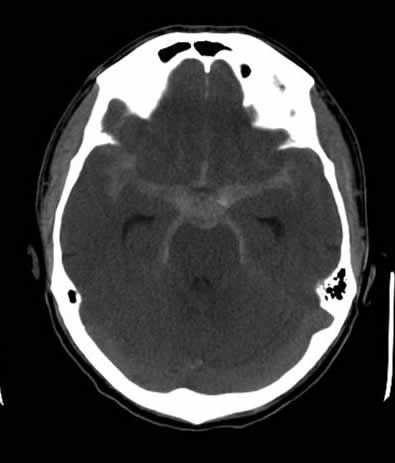

For evaluation of the worst headache of his life, a CT of the brain without contrast was obtained which revealed a subarachnoid hemorrhage (See Figure 2A). CT angiography revealed a basilar artery aneurysm which was successfully coiled (See Figure 2B).

Figure 2

CT scan of the brain showing diffuse subarachnoid hemorrhage CTA showing basilar artery aneurysm with coil in place

Figure 2A. CT scan of the brain showing diffuse subarachnoid hemorrhage Figure 2B. CTA showing basilar artery aneurysm with coil in place